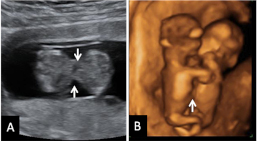

He aquí un signo inequívoco de bienestar fetal: los movimientos vigorosos de un bebé en su semana 12 de gestación. La ecografía 4D muestra al niño en movimiento, junto con la placenta y el cordón umbilical dentro de la cavidad uterina.

Ecografía en 4D de feto de 12 semanas en movimiento

La variedad de movimientos de este bebé de 12 semanas de gestación es muy amplia. Las imágenes muestran cómo cambia de postura varias veces y agita con energía brazos y piernas. Para los ginecólogos, los movimientos de la criatura indican vitalidad, son un signo positivo de salud fetal. En la ecografía en 4D (vídeo) se aprecian casi todas las estructuras externas de la criatura, además del cordón umbilical y la placenta (ambos conectados entre sí), en el margen superior izquierdo de la cavidad uterina.